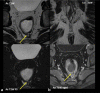

Perianal fistulizing Crohn's disease represents a severe phenotype associated with significant morbidity. Patients with perianal fistulizing disease are more likely to have a severe disease course and have significant reductions in quality of life. Moreover, these patients are at risk for the development of distal rectal and anal cancers. Given the complexity and severity of this patient group, the management of perianal Crohn's disease must be undertaken by a multidisciplinary team. The gastroenterologist and colorectal surgeon play a critical role in the diagnosis and management of perianal fistulizing disease. An examination under anesthesia provides critical information and is an essential part of the work-up of complex perianal fistulas. The radiologist also plays a central role in characterizing anatomy and assessing response to treatment. Several imaging modalities are available for these patients with magnetic resonance imaging as the imaging modality of choice. Perianal disease developing after ileal pouch-anal anastomosis represents a particularly challenging form of fistulizing disease and requires a multidisciplinary clinical and radiologic approach to differentiate surgical complications from recurrent Crohn's disease.